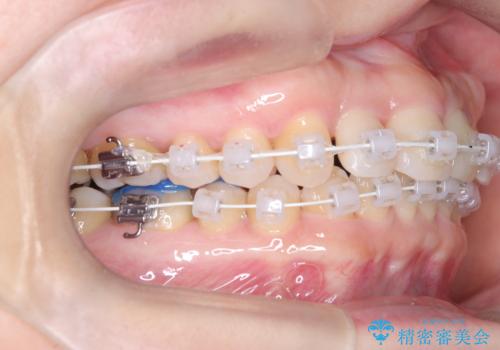

八重歯と口元のバランスを整えた矯正治療

- 「八重歯をきれいにしたい」とのご希望で来院されました。診察の結果、上顎犬歯の萌出スペースが不足しており、典型的な八重歯(叢生)の状態でした。上下の歯の中心(正中)のずれや、奥歯のかみ合わせ(臼歯関係)のアンバランスも見られたため、単に見た目を整えるだけでなく、全体的な機能改善も必要と診断しました。

初期段階では、リンガルアーチを上顎に装着し、奥歯を少しずつ後方へ移動させていきました。これにより前歯部の歯列に十分なスペースを確保。その後、マルチブラケット(ワイヤー矯正)を用いて、突出した八重歯を正しい位置に誘導しながら、歯並び全体を整えていきました。

治療中は咬合バランスや歯列の中心(正中)の位置にも注意を払い、最終的には上下の正中が一致し、左右の臼歯関係も理想的な形に改善されました。見た目の変化はもちろん、かみ合わせの安定や清掃のしやすさも向上。